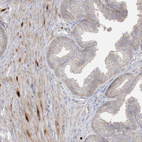

Immunohistochemical staining of human esophagus shows strong nuclear positivity in squamous epithelial cells.